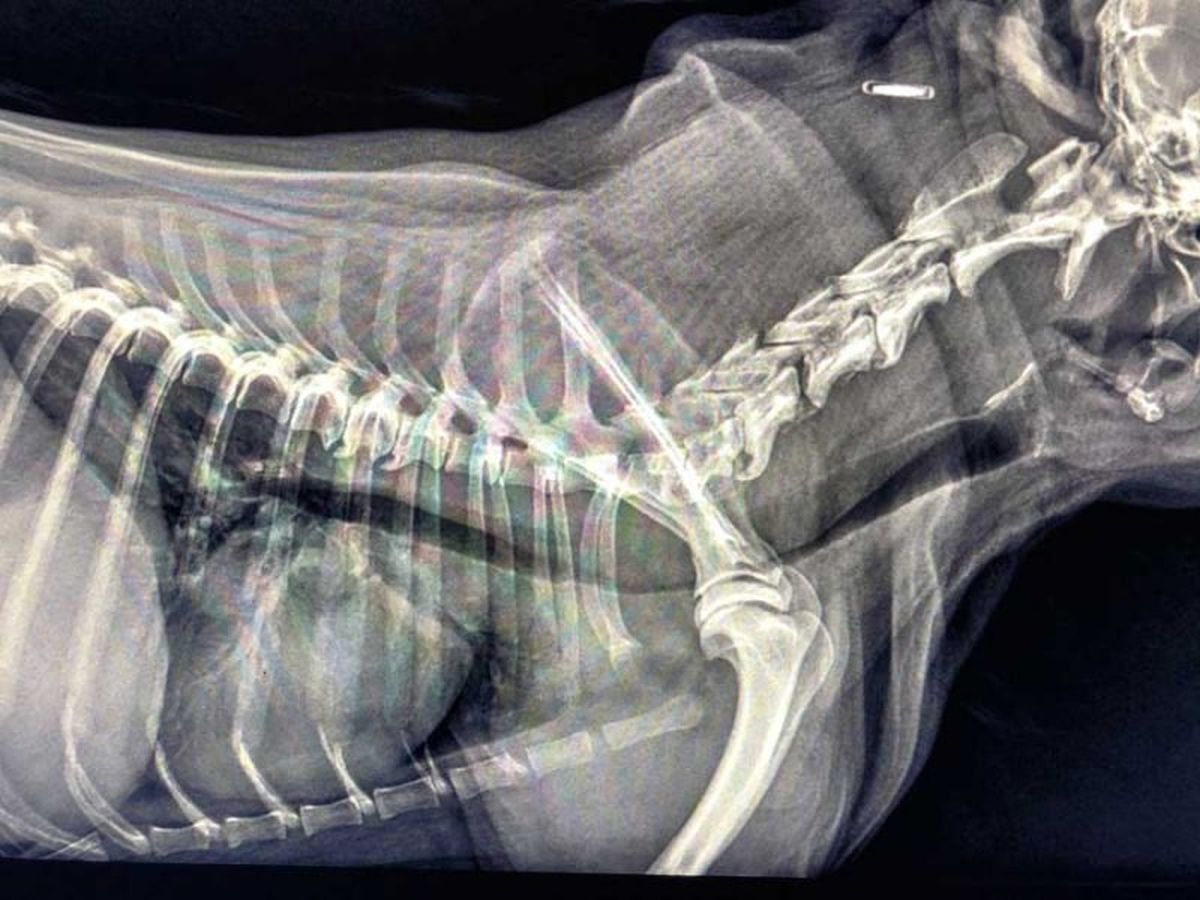

Zapadanie tchawicy u psów (TCS-Tracheal Collapse Syndrome)

Zapadanie tchawicy u psów (TCS-Tracheal Collapse Syndrome) jest przewlekłą chorobą układu oddechowego obserwowaną głównie u raz małych i miniaturowych (Yorkshire terrier, Szpic miniaturowy, Chihuahua). Choroba ta polega na „zapaści” tchawicy co w znacznym stopniu ogranicza jej drożność. Odnotowuje się dwa procesy przyczyniające się do rozwoju tej choroby. Pierwszy z nich, najbardziej klasyczny, to dynamiczna obstrukcja dróg oddechowych, spowodowana chondromalacją i osłabieniem mięśni tchawiczych. Drugi proces, to statyczna obstrukcja związana z malformacją chrząstek tchawiczych i ich układem przypominającym literę „W”.